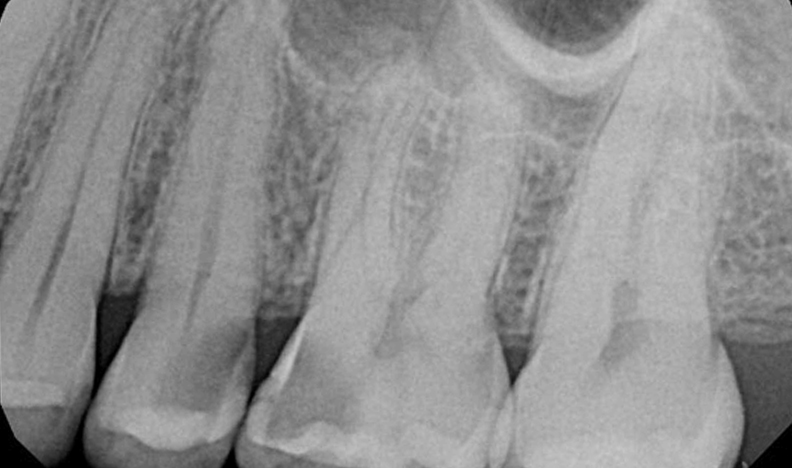

Teeth: 25 and 26

25 – 1 canal, symptomatic irreversible pulpitis, normal apical tissues

Condition of teeth on access: hyperemic